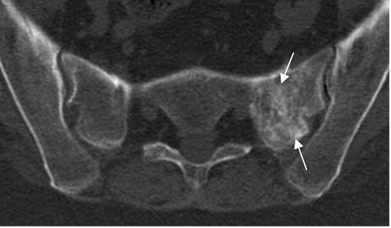

Fig 71. Fractura de stress.

TAC axial. Zona de fibrosis en el alerón izquierdo del sacro, resultado de reparación por fractura de stress.